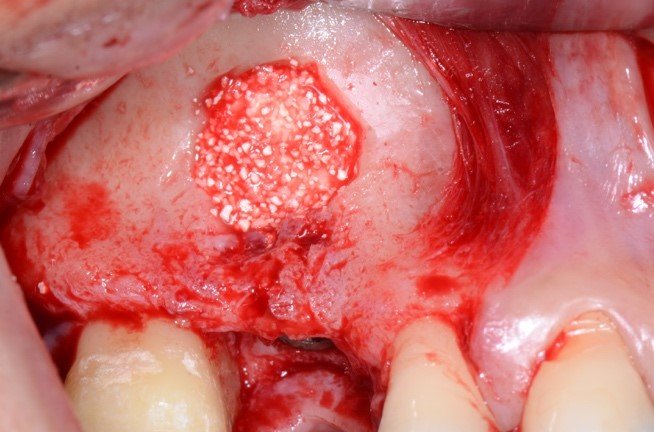

A irrigação da maxila é realizada por ramos de 2 principais vasos, a artéria alveolar superior posterior (AAPS) e a artéria infra-orbital (AIO), ramos da artéria maxilar 3,4. No estudo com tomografias de Khojastehpour et al 5 em 2016, eles encontraram anastomose na membrana entre as artérias AAPS e a AIO em 49.8% dos indivíduos, e do ponto de vista técnico nesssa condição, somente em casos de acidentes com rompimento da membrana sinusal poderia ocorrer hemorragias relevantes. Por outro lado, outros autores têm encontrado maior número de situações em que a AAPS se encontra intra-óssea, como nos estudos de Güncü et al 6 em 2011, e Ilgüi et al 7 em 2013, que observaram 68.2% e 71.1%, respectivamente. Quando a AAPS se encontra nessa última condição relatada, ocorre maior risco de dano vascular com hemorragia, especialmente se o canal vascular intra-ósseo for maior que 1 mm de espessura. Em média, alguns estudos têm demonstrado que a distância vertical do canal vascular da AAPS se apresenta próximo de 16 mm 5,7. Porém em casos de reabsorção do rebordo alveolar essa altura pode ser encontrada próximo de 11mm, segundo Rosano et al 4. A recomendação da tomografia como imagem de diagnóstico para identificação e mensuração da AAPS, pode estabelecer modificações estratégicas tanto na osteotomia, em relação ao desenho vertical e comprimento do implante, quanto na metodologia de instrumentação óssea. Podem ser usadas, por exemplo, ponteiras piezoelétricas sob irrigação para melhorar a visualização operatória e diminuir o risco de laceração vascular. As figuras de 1 a 12, demonstram caso clínico de técnica cirúrgica com osteotomia modificada, usando unidade piezo Mectron para remoção da parede lateral e preservar a AAPS, que foi diagnosticada em exame tomográfico durante a fase pré-operatória.

As figuras 16 e 17 mostram o transoperatório de um caso de hemorragia após dano a AAPS durante procedimento de osteotomia para rotação superior da janela óssea. A hemorragia durante a cirurgia trouxe dificuldades na visualização da membrana e a mobilização da janela para o interior da cavidade para formar o teto sobre a membrana sinusal. Somente após o preenchimento total com enxerto ósseo bovino particulado e cobertura com membrana hemostática de colágeno, houve diminuição do fluxo sanguíneo local. Mesmo com a manobra transoperatória, ocorreu a formação de extenso blefarohematoma periorbital e hematoma cérvico-facial. Segundo relato da paciente, o edema palpebral e na região parotídeo-masseterina provocaram dificuldade na abertura palpebral e bucal. As figuras 18 e 19 demonstram os hematomas já em regressão no 110 dia de pós-operatório (PO), já em uso de compressas mornas desde o 70 dia de PO, associado a moderada massagem local para drenagem hemo-linfática nos tecidos com pomada fibrinolítica.